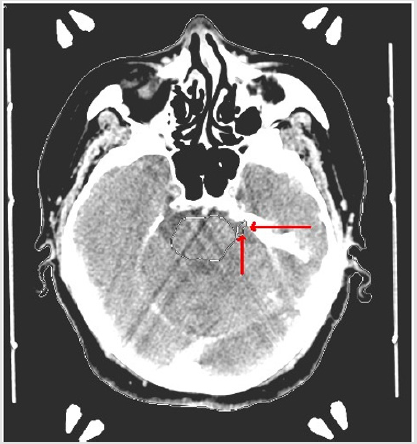

Target volume determination based on CT-only imaging and CT-MR fusion-based imaging was comparatively evaluated. Ground truth target volume defined by board certified treatment team after comprehensive assessment and colleague peer review was identical to target definition using CT-MR fusion-based imaging. Target volume delineation on the planning CT and MR images was optimized by selection of appropriate windows and levels in radiosurgery planning. Contouring accuracy was improved by use of sagittal and coronal images in addition to axial planning CT images. was achieved by use of the Arc Modulation Optimization Algorithm (AMOA) was utilized for optimization of target volume coverage and critical organ sparing. (Figure 1) shows axial planning CT image and (Figure 2) shows the corresponding axial MR image of the same patient with trigeminal neuralgia.